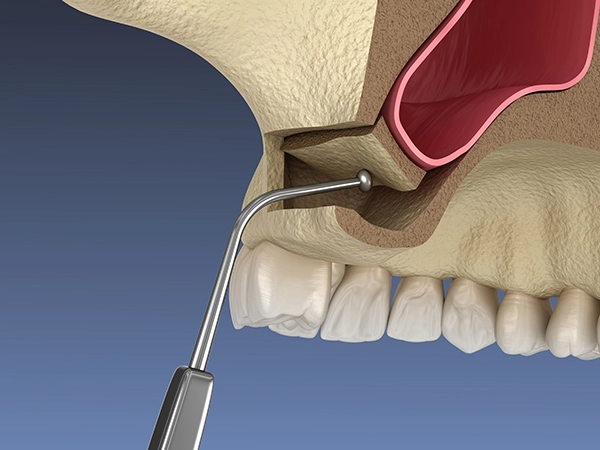

Синус-лифтинг проводится только на верхней челюсти в области гайморовых пазух. Бывает открытый синус-лифтинг и закрытый синус-лифтинг. Вид операции зависит от состояния костной ткани и того, насколько сильна атрофия. Позволяет восполнить объём кости, как в случае единичной потери зуба, так и при множественной. Костная пластика в зоне синусов достаточно распространенная процедура, поскольку костная ткань верхней челюсти разрушаются быстрее, чем на нижней.

Синус-лифтинг проводится только на верхней челюсти в области гайморовых пазух. Бывает открытый синус-лифтинг и закрытый синус-лифтинг. Вид операции зависит от состояния костной ткани и того, насколько сильна атрофия. Позволяет восполнить объём кости, как в случае единичной потери зуба, так и при множественной. Костная пластика в зоне синусов достаточно распространенная процедура, поскольку костная ткань верхней челюсти разрушаются быстрее, чем на нижней.